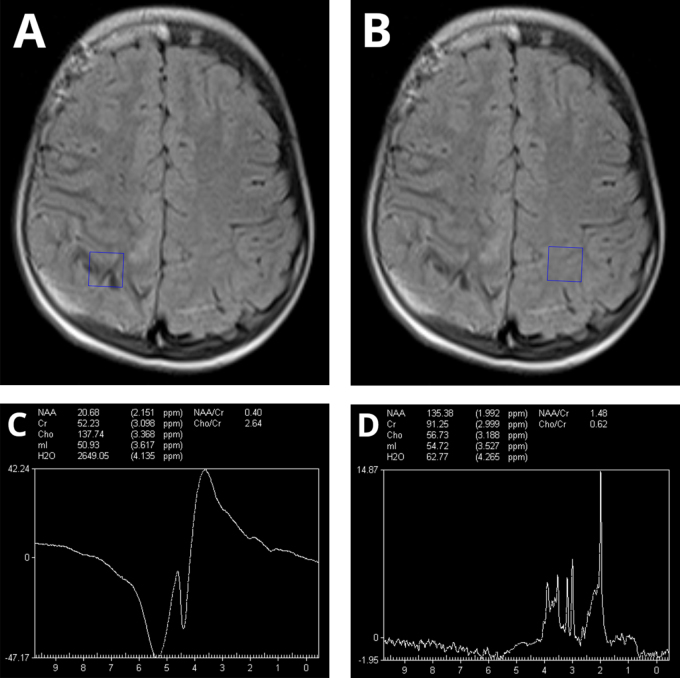

Case presentation: An 11-year-old boy, previously diagnosed with Sturge-Weber syndrome (SWS) Type I, presented to the emergency department with acute neurological symptoms that included vomiting, headaches, left-sided hemiparesis, and right-sided deviation of the labial commissure.

Clinical discussion: Sturge-Weber syndrome (SWS) is a rare neurocutaneous disorder characterized by facial port-wine stains, leptomeningeal angiomas, and ocular involvement. Our case presented with preserved cognition despite extensive temporal lobe angiomatosis, contrasting the typical presentation of seizures and developmental delay. The patient then experienced stroke-like episodes from fragile leptomeningeal vasculature. With anticonvulsants and low-dose aspirin therapy, the patient achieved full neurological recovery within the first 3 months and maintained stability during 2 years of follow-up.